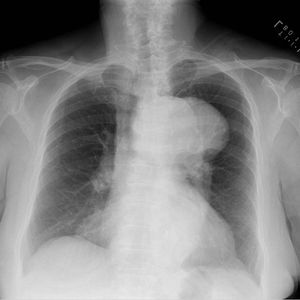

Aortic arch aneurysm

X-Ray showing Massively enlarged transverse aortic arch aneurysm in a 76 y/o woman.